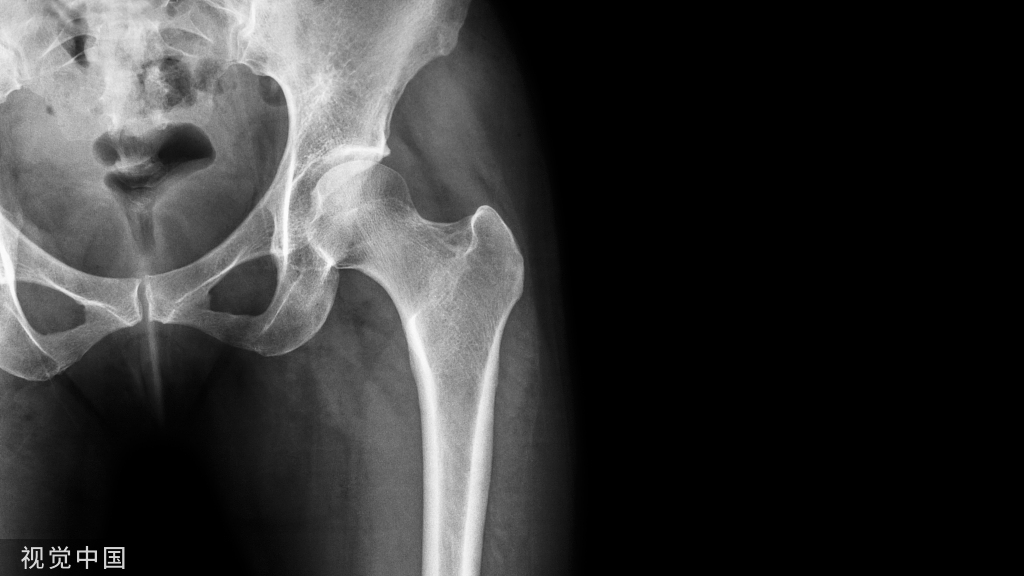

股骨粗隆骨折,术中如何正确开口?

具体操作

首先,我们要在大粗隆近端做一个2~3公分的小切口,建立一个良好的软组织通道。对年龄比较大的、骨质比较疏松的病人,为了减少手术时间,可采用开口器直接开口,直接插钉的方法。开口的同时要特别注意,手指先摸到大转子顶点偏内侧,然后,开口去顺着手指方向插入,开口器一定要紧贴着身体轴线。